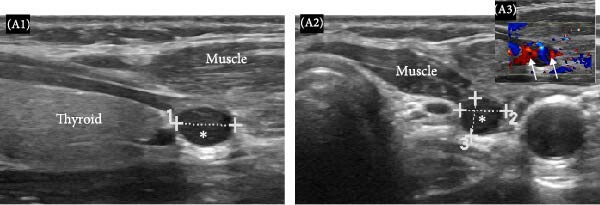

Послеоперационное наблюдение осложнилось синдромом голодной кости, который был успешно купирован в стационаре. Пациентка была выписана с назначением перорального препарата кальция в поддерживающей дозе и холекальциферола. Спустя 2 года она обратилась повторно в связи с появлением пальпируемого безболезненного претрахеального узелка вдоль послеоперационного рубца. Лабораторные исследования выявили высокий уровень кальция (12,7 мг/дл), ПТГ (185 пг/мл) и низкое содержание фосфора (2,9 мг/дл). С помощью УЗИ были обнаружены множественные гипоэхогенные четко очерченные узелки, похожие на аденомы паращитовидных желез (рис. 6-7).

Рисунок 6. Продольные (A1) и поперечные (A2, A3) серо-шкальные УЗ изображения левой доли щитовидной железы, где виден овальный четко очерченный гипоэхогенный узел размером 6,5 мм×5 мм×4,2 мм (A1, A2), прилегающий к нижнему полюсу левой доли щитовидной железы в месте паратиреоидэктомии. При проведении допплерографии заметна повышенная васкуляризация (стрелки на A3).